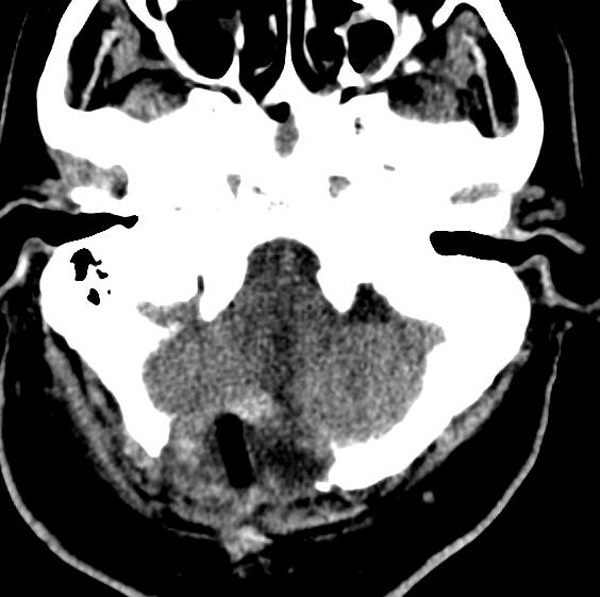

12月27日,陕西省核工业二一五医院成功为一名73岁患者行延髓肿瘤切除术,此次手术为咸阳市首例,填补了咸阳地区级医院独立开展脑干肿瘤切除的技术空白,标志着二一五医院在脑干病变的诊疗技术上再上新台阶。 73岁的刘...